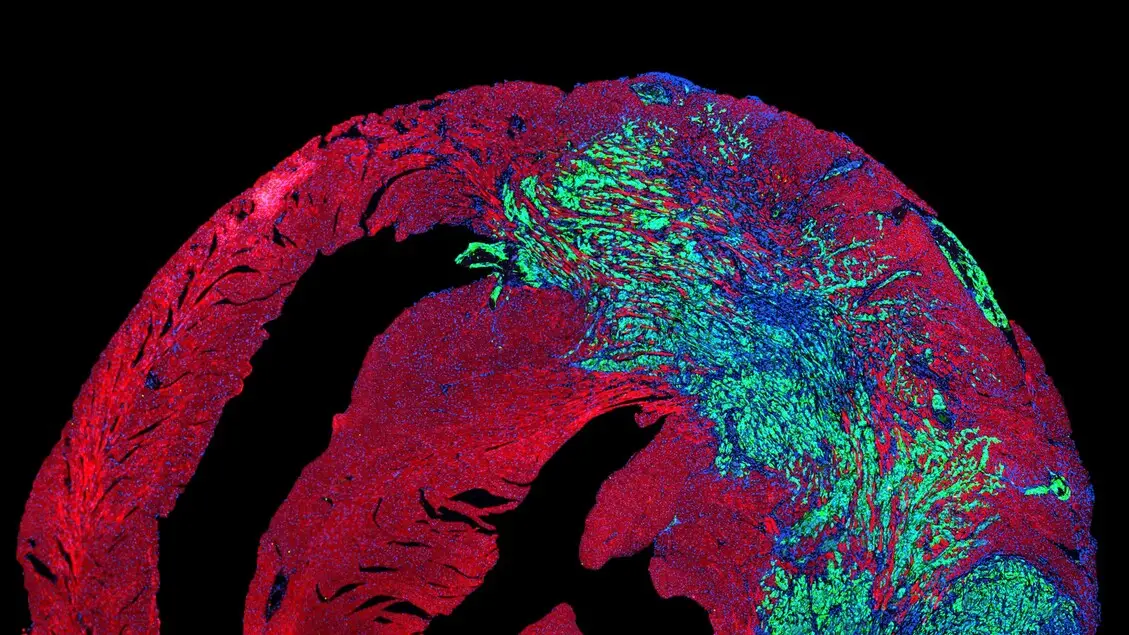

Il battito del cuore apre una nuova strada per combattere i tumori

E' quella della stimolazione meccanica